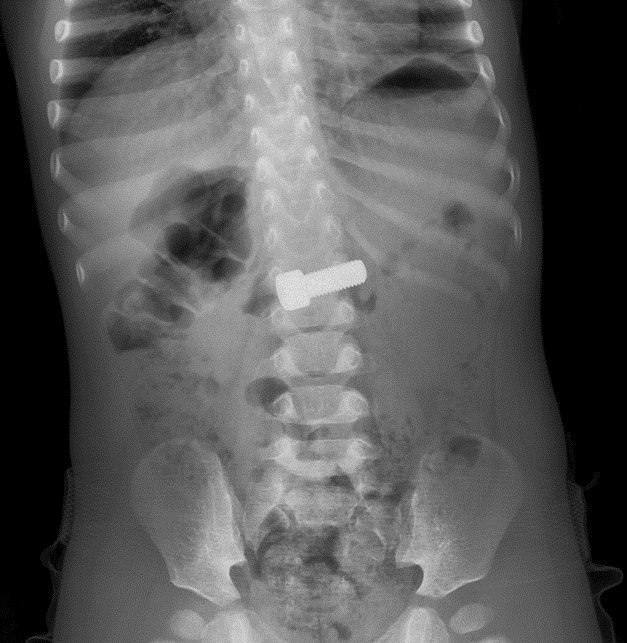

Эндоскописты Детского научноклинического центра им. Л. М. Рошаля помогли годовалому мальчику, который случайно проглотил металлический болт.

Рентген показал крупное инородное тело в желудке. Врачи провели малотравматичную эндоскопическую операцию — без разрезов, с помощью специальной петли. Процедура заняла около 15–20 минут.